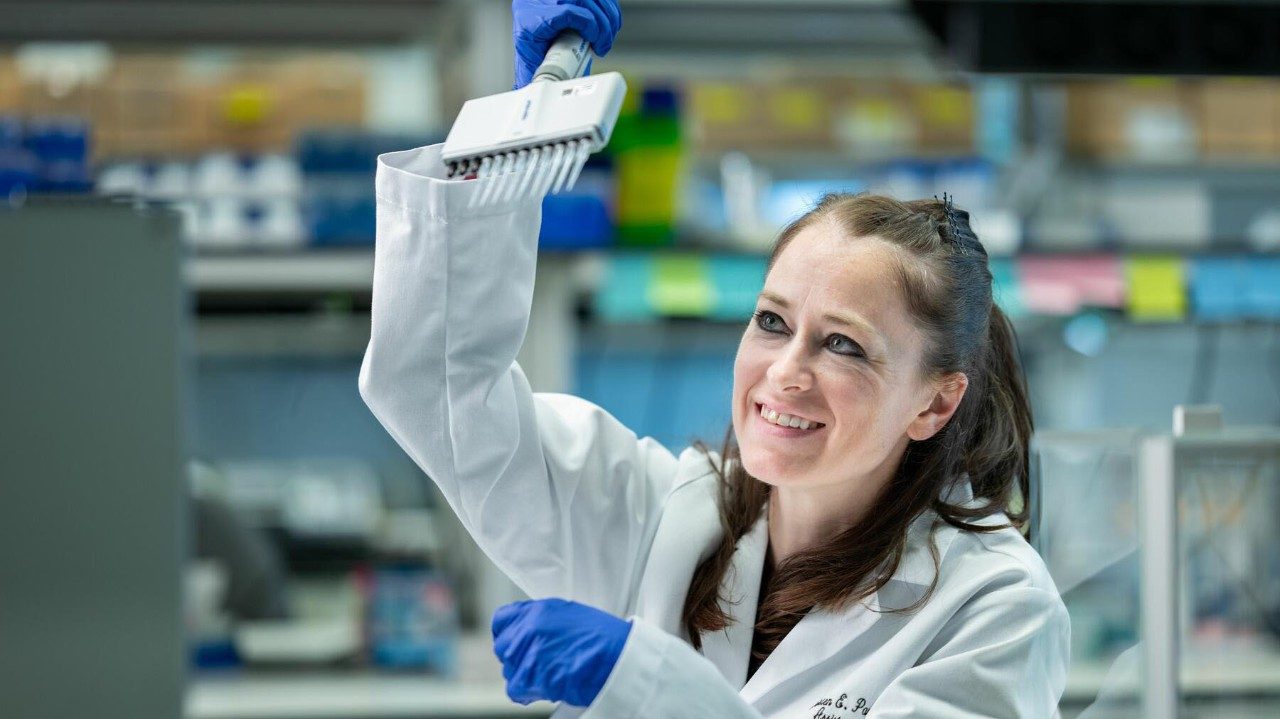

After conducting additional tests, Iheme and the rest of my care team — including breast surgical oncologist Dr. Taiwo Adesoye and breast radiation oncologist Dr. Melissa Mitchell — recommended a Phase 2 clinical trial with a novel HER2 targeted therapy drug in combination with endocrine therapy. It involved a new bispecific antibody called zanidatamab that was already being used successfully to treat HER2+ metastatic breast cancer, bile duct cancer and other gastric cancers. The preliminary results of the Phase 2 clinical trial were promising. So, I agreed to take part.

Breast medical oncologist Dr. Vicente Valero, who was leading the clinical trial, agreed. He called it “a very robust response.”

By the time I finished the clinical trial, my breast was totally clear, so I could have a lumpectomy instead of a mastectomy. The pathology report showed I’d had a complete pathological response. There was no evidence of residual cancer in my breast or lymph nodes.